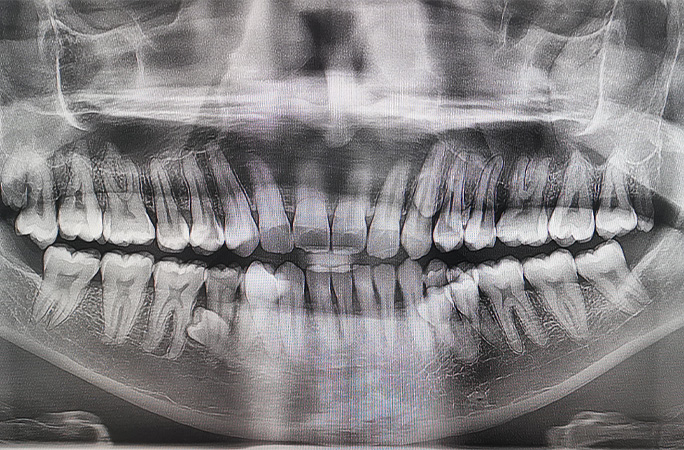

その本数は42。一般の人たちより10本多いのです。

ギネス世界記録「最も歯の多い男性|most teeth in a person's mouth (male)」に認定されているプラタブさん。2023年に、ふたりの歯科医に検査してもらい、歯の数を確認しました。

さらに驚きなのは、レントゲンを確認すると、さらに2本の歯が埋もれているというのです。

「数えたら、当時は38本ありました。レントゲンをとってもらったら、あと4本埋もれていることが分かりました。ありがたいことに、後から出てきた歯はトラブルなくまっすぐ生えてきてくれました」